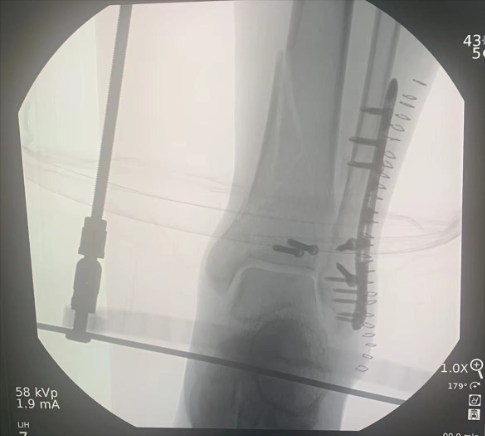

術(shù)中圖: